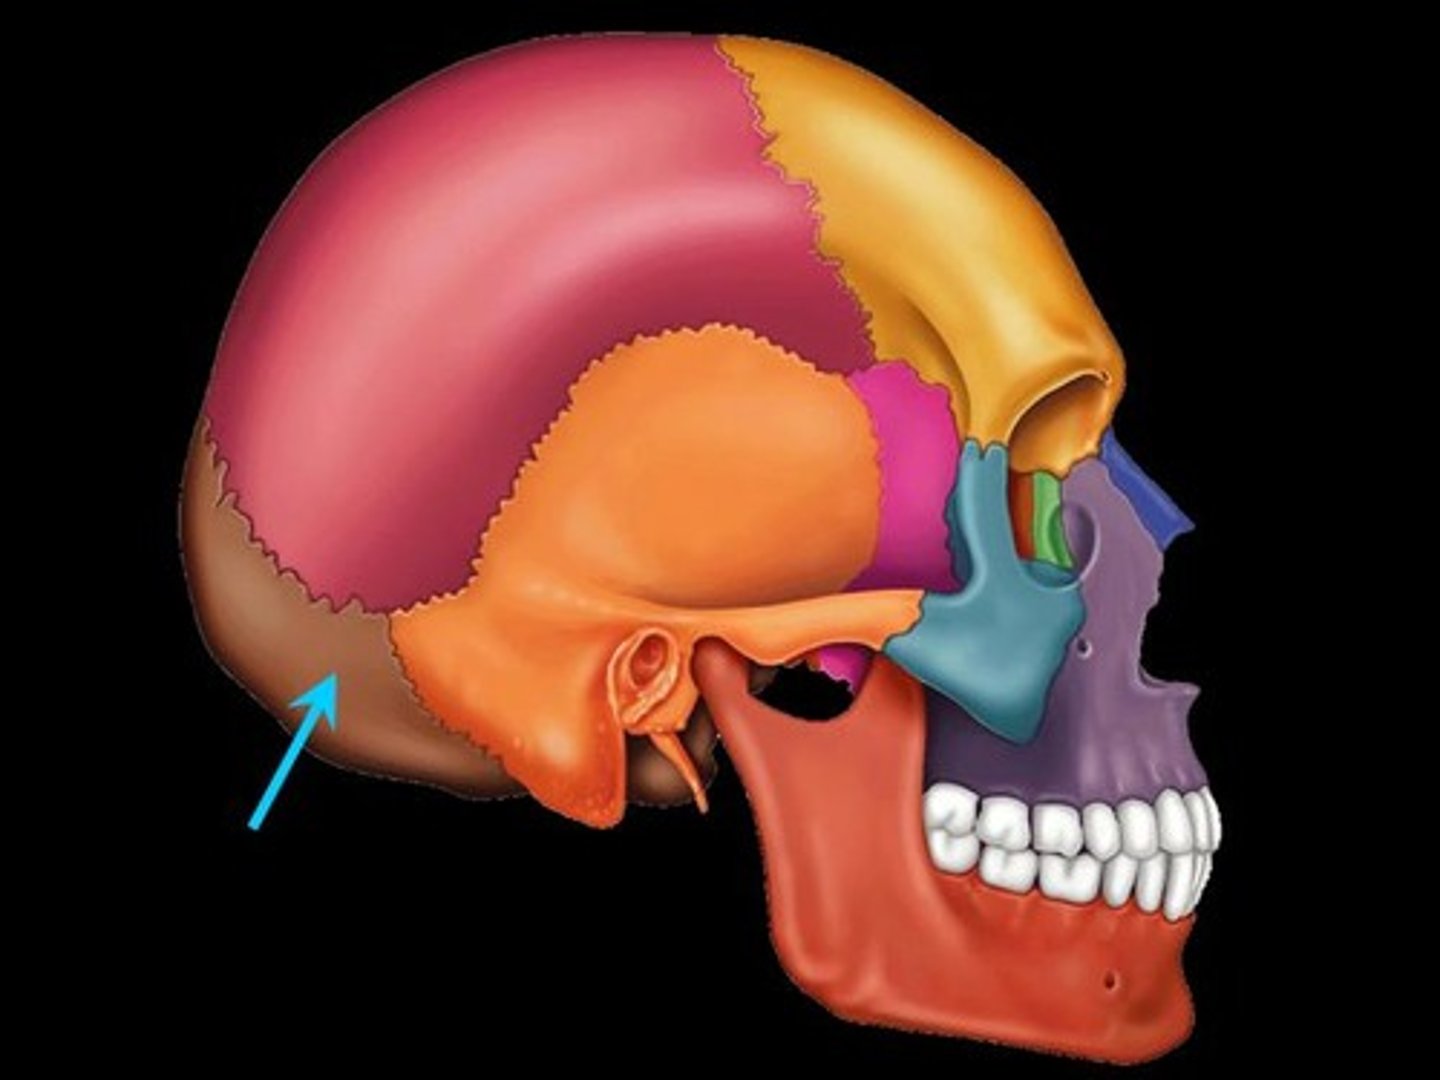

Occipital Bone

forms the posterior floor and walls of the cranium